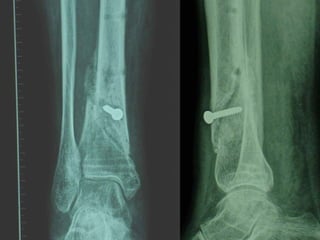

Rx post

Dal Gennaio 2000 al Febbraio 2006 abbiamo trattato 167 fratture chiuse  con placca percutanea  in 164 pazienti :  27 lesioni diafisarie di gamba, 12 piloni tibiali ,  11 fratture prossimali di tibia, 36 fratture sovracondiloidee di femore, 17 fratture diafisarie di femore, 43 fratture metaepifisarie prossimali di omero, 21 diafisarie d’omero.  156 guarigioni 8 fallimenti

Dal Giugno 2002 al Dicembre 2004 abbiamo trattato 5 fratture esposte: 3 di tibia e 2 di ulna 5 guarigioni